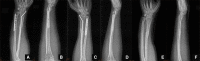

Case report: We report a case of a 29-year-old male patient with both bone forearm fractures. Temporarily closed reduction and plaster external fixation were performed in the emergency room, and the patient was admitted to the orthopedic trauma ward for surgery. The patient underwent open reduction and plate fixation of the ulna and closed reduction and ESIN fixation of the radius. The fractures healing was satisfactory and the internal fixation was removed 12 months postoperatively.